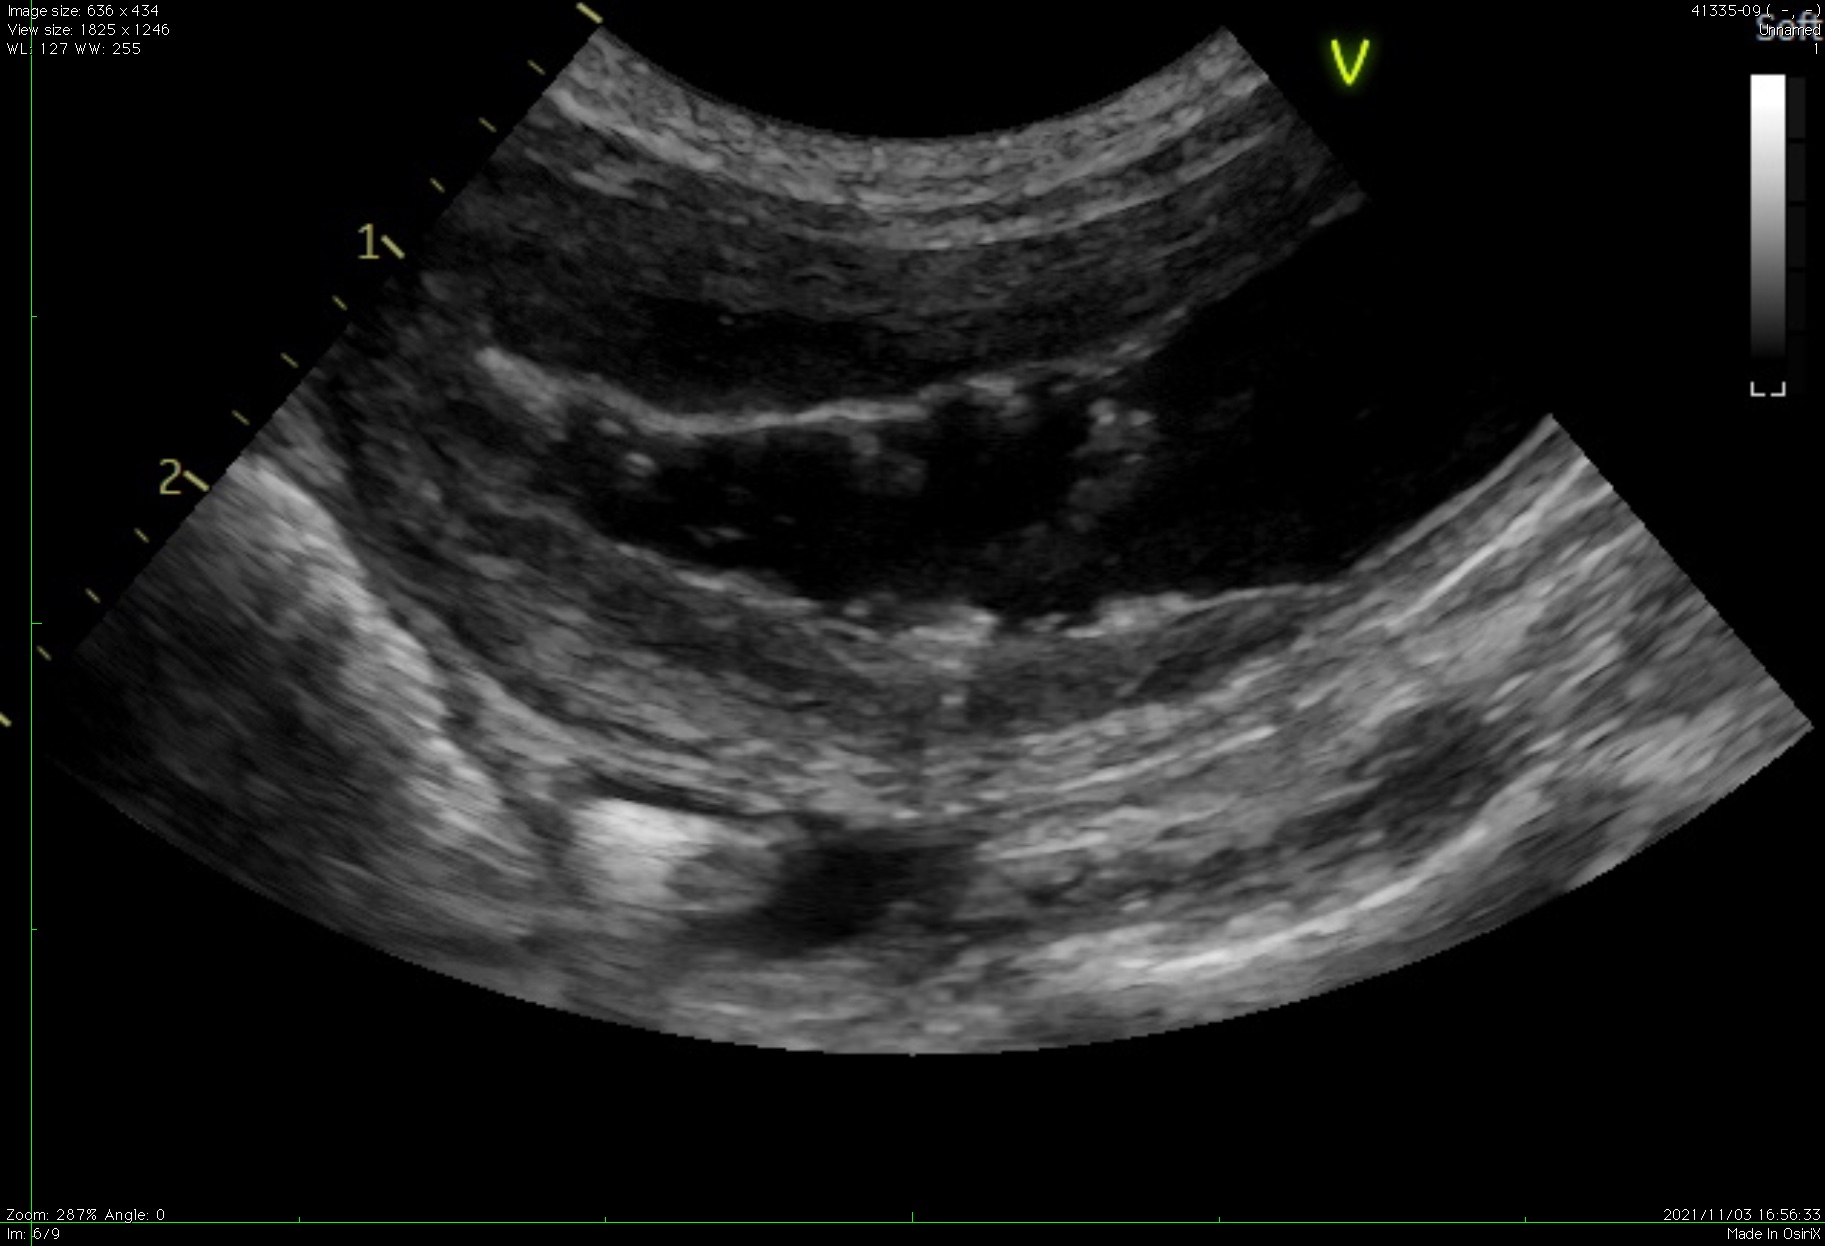

特発性膀胱炎で粘膜が肥厚している様子